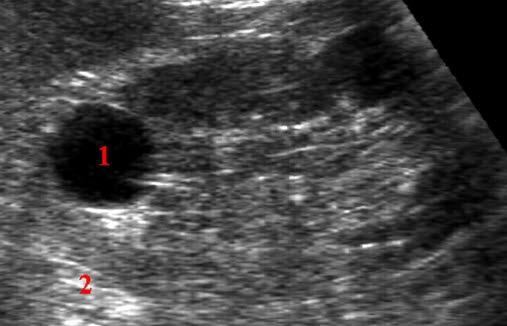

Nyrecyste - ultralydbildeEn nyrecyste er et væskefylt hulrom, en såkalt cyste, som man vanligvis finner i de ytre deler av nyre, i det som kalles nyrebarken. Slike cyster har normalt ingen sammenheng med sykdom og er så godt som alltid godartede.

De fleste nyrecyster medfører ingen symptomer, men noen cyster kan gi episoder med smerter i flankene eller blod i urinen. Cystene er vanligvis små, ovale eller runde tynnveggede sekker fylt med vann. Nyrecyster forekommer svært ofte, og finnes hos ca. 15% av tilfeldig undersøkte voksne personer. Forekomsten øker med økende alder.

Nyrecyster oppdages som regel tilfeldig, og de kan for eksempel ses ved ultralyd, CT eller kontrastrøntgen.

Oftest påvises cysten ved ultralyd. Ved denne undersøkelsen kan leger som er godt trente i denne teknikken, i de flest tilfeller med sikkerhet fastslå om cysten er godartet og uskyldig, eller om det er nødvendig med ytterligere undersøkelser.